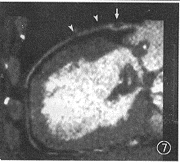

图6 与图5同一病人行EBCT检查,中心线重组显示左主干(箭标)和前降支(箭头)的重度狭窄

图7 与图6同一EBCT数据,曲面重组显示左主干(箭标)和前降支(箭头)的重度狭窄

MAR和CPR处理的正常冠状动脉EBCT造影图像分别示于图3、4,1例病变冠状动脉的造影、MAR、CPR图像分别示于图5~7。从中可以看出MAR具有以下特点(图3~12)。